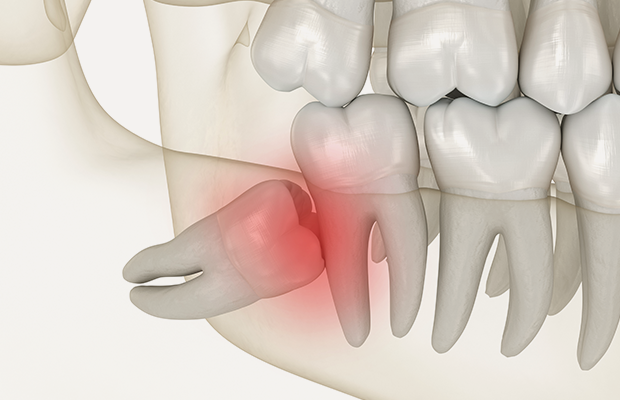

사랑니 발치

사랑니는 잇몸 속에 비정상적으로 매복되거나,

주변 치아에 문제를 일으킬 수 있어 방치 시 치아

이동이나 염증의 원인이 됩니다.

3D CT로 위치와 형태를 정확히 파악한 뒤, 경험

많은 의료진이 안전하게 발치합니다.